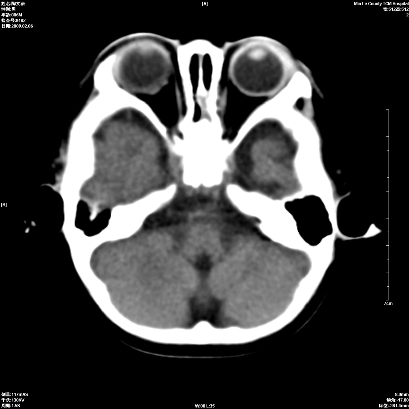

以下是引用wxq2008在2009-2-6 17:01:00的发言:[br]hie后遗症脑萎缩。

以下是引用学医在2009-2-6 21:45:00的发言:[br]hie后遗改变